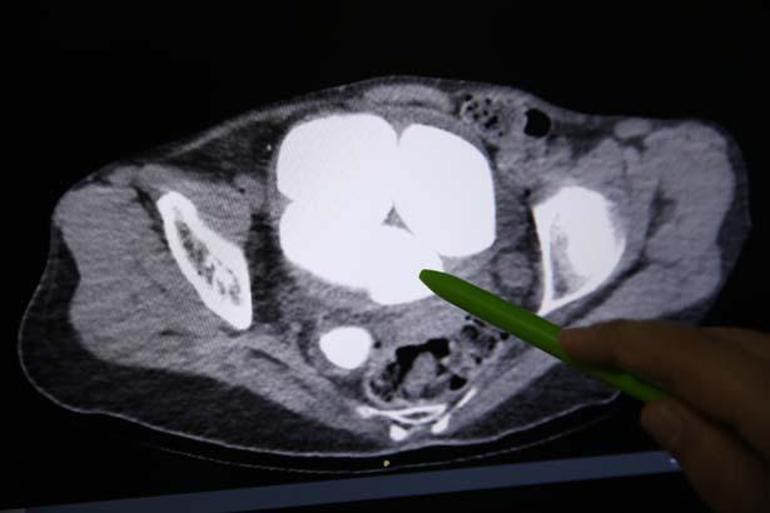

Üroloji Bölümünde Opr. Dr. Süleyman Çankaya tarafından yapılan tetkiklerde, hastanın mesanesi ve idrar kanalında en küçüğü 2, en büyüğü 9 santimetre olan 6 taş tespit edildi.

Bu rahatsızlığın sık olmasından dolayı tomografi de çekildiğini ifade eden Çankaya, “Tomografi sonucunda böbreklerin zarar gördüğünü, böbreklerde genişleme olduğunu tespit ettik. İdrar kesesinde büyük 5 taş olduğunu, sağ böbrek kanalında da idrar kesesine yakın kesiminde yine büyük bir taş bulunduğunu gördük. Hasta zihinsel engelli ve kendisini ifade edemiyor. Bu sonuç üzerine ameliyat kararı aldık.” dedi.

“Hastanın idrar torbasında gördüğümüz taşları ve idrar kanalının tam idrar torbası ile birleşim yerindeki taşları açık operasyonla çıkardık. Hastanın kliniğimizde yatış, ameliyat ve taburcu süreci 3 gün sürdü. İdrar yolu enfeksiyonun tedavisi halen devam etmekte. Böbreklerin idrar torbasındaki taşlar ile hasarlanması nedeniyle aynı seansta idrar kanalından böbreğe uzanan, böbreklerin eski fonksiyonuna dönmesini sağlamak amacıyla stent uyguladık. Normalde idrar torbasında, idrar kanalında gördüğümüz taşlardan hacimce çok çok büyük taşlar. Az rastladığımız taş şekillerinden. Uyguladığımız stent ile böbrekteki hasarın geriye dönük normalleşmesini beklemekteyiz.”